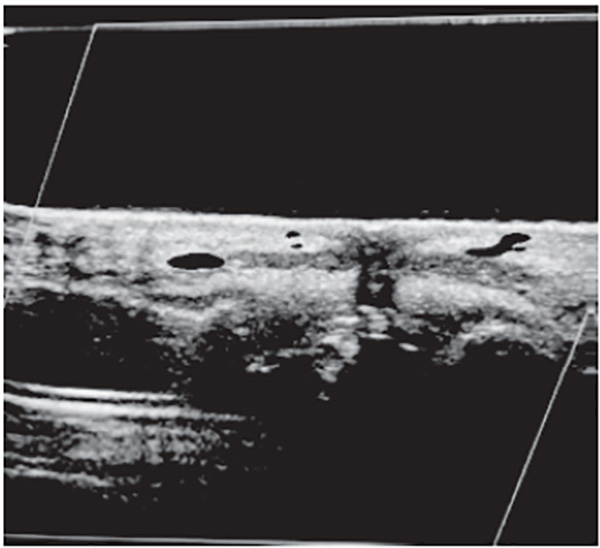

The highly hydrophilic nature of commercial HA gels provides an ideal acoustic appearance on ultrasound. HA acts like fluid, when properly hydrated, appearing anechoic to hypoechoic, with good acoustic transmission. HA does have a variable appearance dependent on filler viscosity, age, and degree of tissue biointegration [68]. Freshly injected HA may not have a significant acoustic footprint and can be imperceptible to normal tissue; it is only when hydrated/fluid-bound and hydrophilic that it appears anechoic to hypoechoic, particularly with highly viscous HA preparations [69]. Acoustic enhancement posteriorly is a property of HA and hydrophilic preparations. An example of supraperiosteal placement of hyaluronic acid filler is illustrated inFigure 3.

Of the two commonly used temporary cosmetic fillers available commercially, HA filler is the most widely recognized and used [93]. Hydrated HA filler has an anechoic to hypoechoic appearance (similar to simple fluid), and stands out as distinctly darker than surrounding tissues, such as skin, dermis, and muscle. Some heterogeneity within the filler could be encountered, depending on age and maturity of the filler, probably the result of biointegration into surrounding tissues [94].

Typical ultrasound appearance of unwanted or residual HA filler is anechoic to hypoechoic, suggesting that the filler is reasonably well hydrated. One protocol consists of targeted treatment using microinjections of 15 IU, not exceeding 150 IU in total, administered in a radial pattern within unwanted (anechoic or hypoechoic) hydrated filler, dependent on volume of residual HA filler. Large quantities of HA filler (greater than 3 mL) could require repeat injections at one- or two-week intervals. Use of high-dose dose hyaluronidase flooding protocols (greater than 150 IU in a single session) is discouraged because of potential leakage into surrounding body tissues, risking an extended area of potential tissue breakdown. The effects of treatment are generally immediate, and a follow-up targeted ultrasound of the area shows no residual Ha filler (Figure 4) [98].